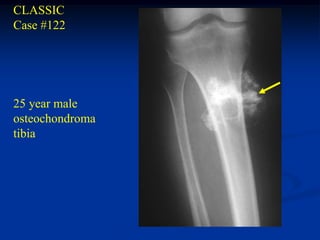

CLASSIC

Case #122

25 year male

osteochondroma

tibia

Lateral view

cartilage cap

fatty marrow

Sagittal T-1 MRI

Macro section